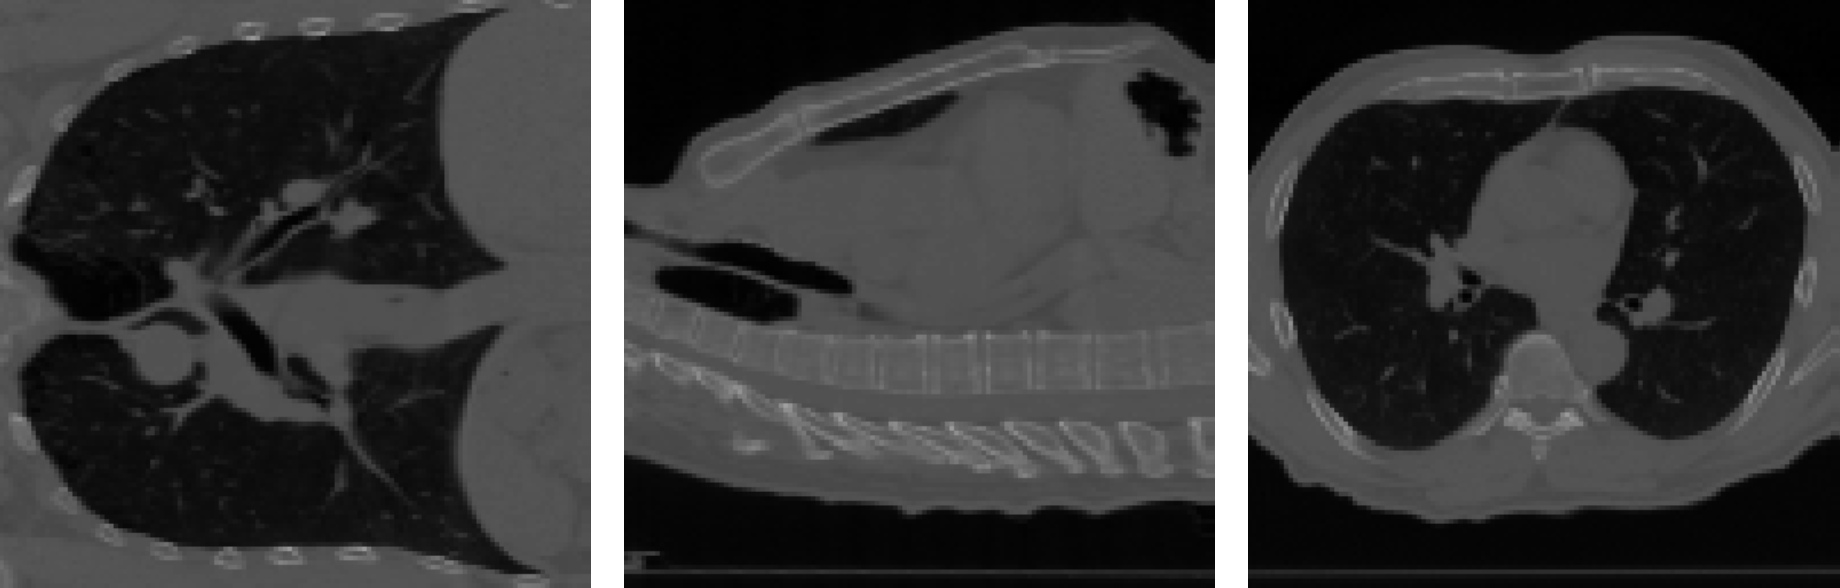

In this section, we show the capability of the proposed three formulations in Section 3.2.4 in real data. The 4DCT dataset, consisting of two lung CT scans featuring 300300 pairs of landmarks, is chosen for demonstration. This dataset can be accessed through the Deformable Image Registration Laboratory (www.dir-lab.com).

Following ZhangDaoping2022AUFf , we resized the images to 1283128^{3} and normalized the pixel values to the range [0,1][0,1]. Unless otherwise specified, we empirically selected α1=0.01\alpha_{1}=0.01, α2=50\alpha_{2}=50, α3=1\alpha_{3}=1, α4=0\alpha_{4}=0, α5=500\alpha_{5}=500, and α6=500\alpha_{6}=500 in (18). In Fig. 7, we present snapshots of the resulting 3D mappings, along with the histograms of detfθ\det\nabla f_{\theta} and the training losses for various variational models. From Fig. 7 and Table 3, we make the following observations:

Additionally, Fig. 8 displays various slice views of the source image SS, target image TT, warped image SfθS\circ f_{\theta}, and their respective absolute differences. These results highlight the effectiveness of incorporating intensity information into our framework.

Figure 8: The 4DCT Lung CT example. Visualization of the registration results via three slice views, i.e., x=0.5,y=0.5,z=0.5x=0.5,\,y=0.5,\,z=0.5. (a)-(b) Three views (slices) of the source image SS and target image TT, respectively. (c) Three views of the absolute difference between SS and TT. (d)-(e) The landmark matching registration results. (f)-(g) The intensity matching registration results. (h)-(i) The hybrid matching registration results.